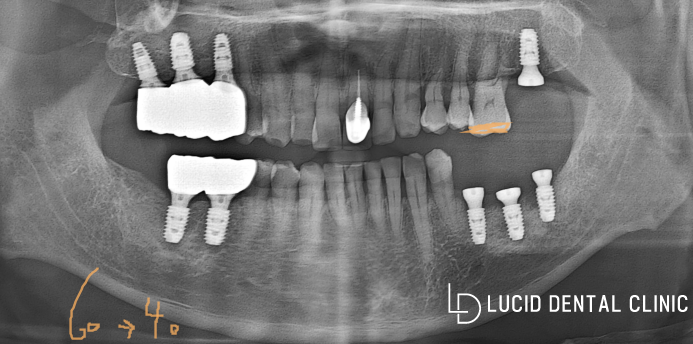

- 임플란트 수술 후

타원에서 심어놓은 픽스처는 제거하고,

말씀드린 대로 가이드 장치를 이용하여

원데이 당일 픽스처 식립을 마쳤는데요

치은의 모양을 예쁘게 만들 수 있도록

어버트먼트 또한 위치에 맞게

체결하여 마무리했어요.

- 임플란트 수술 종료

루시드 역삼동 치과 에서 제작한

보철을 체결해 드리며 종료했는데요

사진을 기준으로 오른쪽 부위는

아직 회복이 마무리되지 않아

조금 더 기다리기로 했습니다.

보철은 최대한 이질감 없이 조화로우며

환자가 원하는 색조에 맞춰 제작했는데요

다행히 마음에 든다고 말씀하셔서

교합 높이와 매끄럽게 다듬어 주는

작업을 통해 최종적으로 종료했습니다.